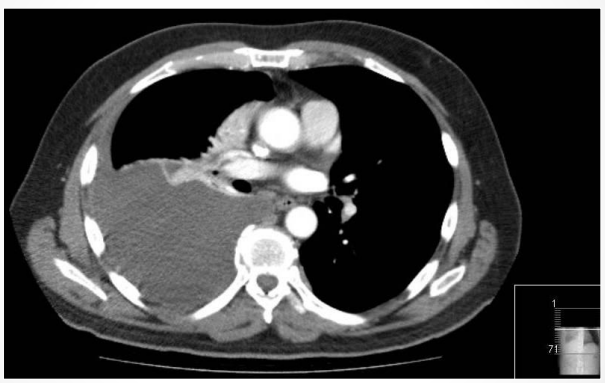

4

Q

This image shows a chest CT of the lungs. What pathology is depicted? [1]

A

Mesothelioma